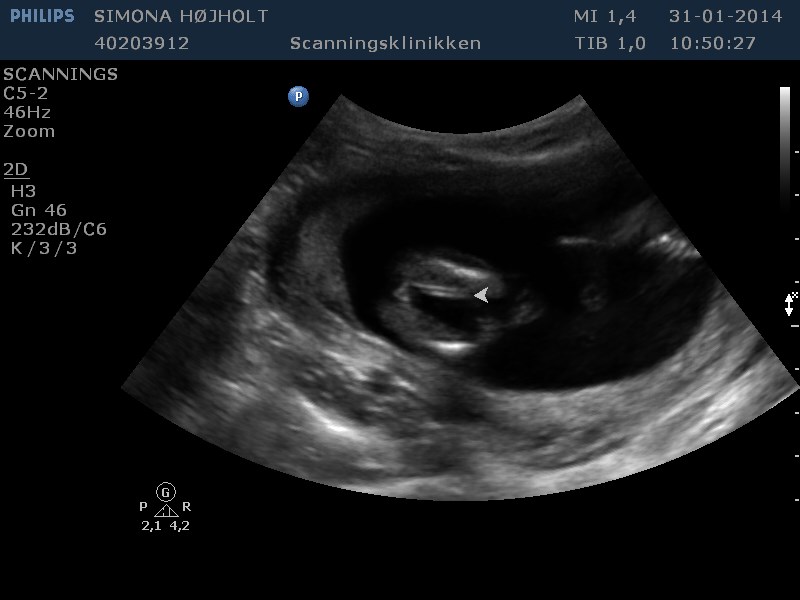

Ja, hvad skal vi have?

Svaret kender jeg, men kan I se det? ;-) Altid godt med lidt træning og gætterier!

Vedhæftede fotos (klik for at se i fuld størrelse)

Umiddelbart synes jeg at kunne se to streger på de nederste to billeder så jeg gætter på en pige